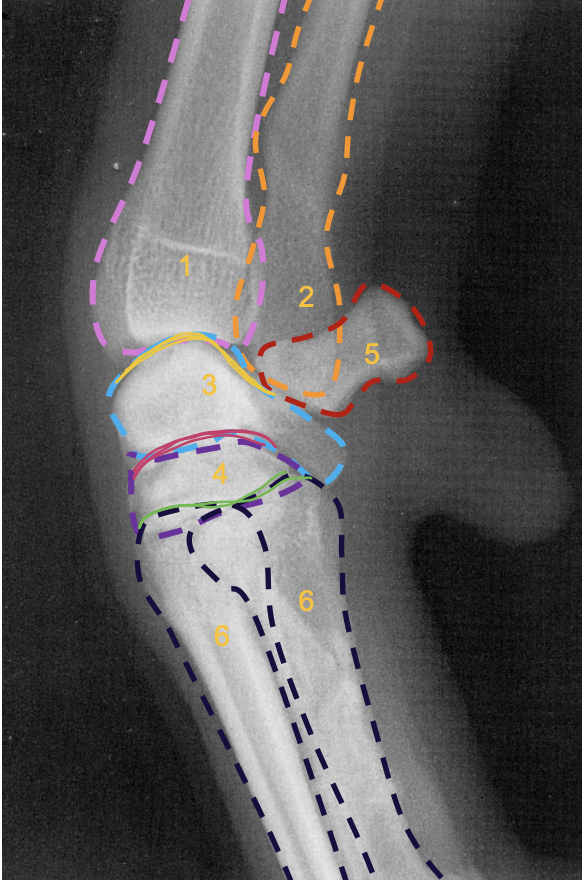

what is the pink line?

medial epicondyle of the humerus (makes 90 degree angle)

what is the purple line?

lateral condyle of humerus

what is the light blue line?

medial condyle of humerus

what is the green line?

medial coronoid process of the ulna

what is 8?

olecranon process of the ulna

what is the arrow at 8 pointing to?

physeal scar on distal physis of the radius